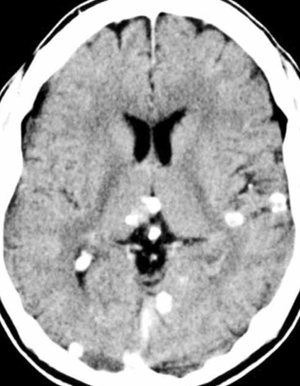

- Most cases are asymptomatic and discovered incidentally after resolution of infection (see image below)

- CT head (calcifications/edema); MRI (cysts +/- scolex, edema)[3]